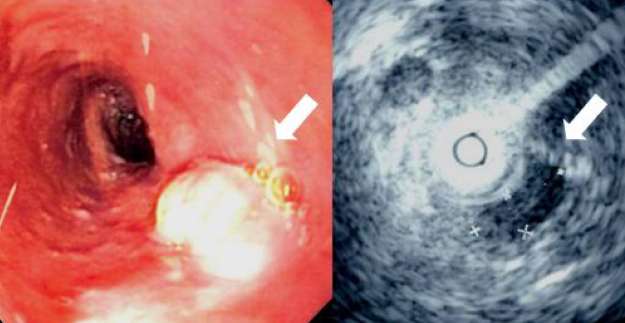

Kansarkan oo ku dhaca hunguri-mareenka, afka qalaadna lagu yiraahdo “Eosophageal Cancer” wuxuu ku billowdaa buro yar oo ka soo baxda hunguriga, taas oo marba marka ka dambaysa weynaata ilaa ay xirto marinka hunguriga, waxayna badanaa ku dhacdaa qaybta hoose ee hunguriga.

Qofka xanuunkan qabaa wuxuu badanaa isbitaalka yimaaddaa marka wax liqiddu ciriiri ku noqoto, taas oo ah xaalad culus, balse, ka hor wuxuu isku arkaa: miisaanka oo dhaca, liqidda oo dhib ku noqota, codka oo xabeeb yeesha, qufac, iyo xabbad xanuun.

Kansarka ku dhaca hunguri mareenka waxaa loo arkaa, walaac ka soo shaac baxaysa Soomaaliya, marka lala barbardhigo noocyada kale ee kansarka. Habka ugu muhiimsan ee looga hortagi karo ayaa ah, in marka isku aragto, in cunnadu ku dhibayso ama cadaadis xagga hunguri mareenka aad ka dareento, in aad dhakhtar si dhakhso ah u la xiriirto.

Waxyaabaha loo malayn karo, in kansarkaan ka qeybqaataan waxaa ka mid ah; wax kasta oo dhaawac gaarsiin kara hunguriga, sida: cabbidda khamriga, laab jeexa joogtada ah, cabbidda waxyaalaha kulkulul, sida: shaaha, cunidda miraha iyo cagaarka oo la yaraysto, gaas calooleedka, sigaarka, iyo raajo isa saaridda feeraha oo la joogteeyo.